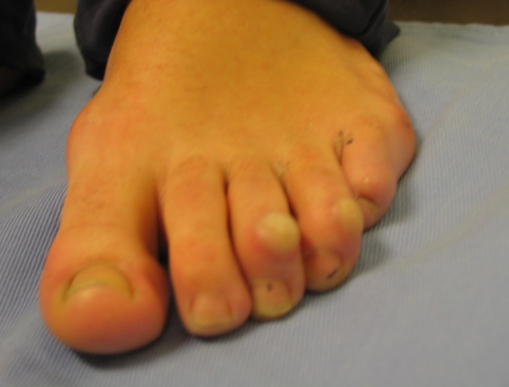

Hallux valgus (juanete) y dedos en garra

Hallux valgus (juanete) y dedos en garra: antes Hallux valgus (juanete) y dedos en garra: después